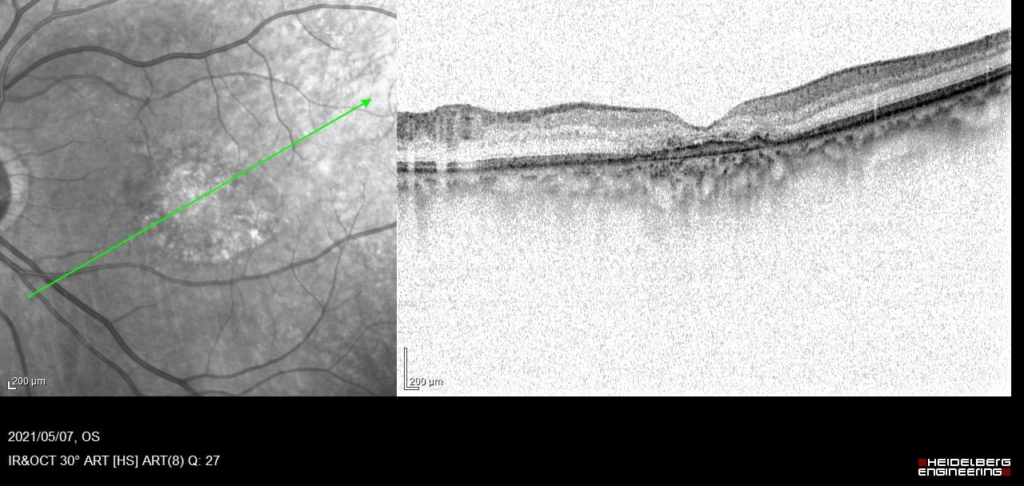

漿液性網膜剥離 Serous Retinal Detachment(SRD)がみられる。RPEは不正に隆起し、double-layer sign(RPEを示す高反射層とそれより外層にみられる高反射層の間に間隙がみられる)がみられ、CNVの存在を示す。

Cross Sectional-OCTA(CS-OCTA BモードOCTA画像)ではdouble-layer signを示す隆起したRPE下に血流信号(赤色)がみられる。漿液性網膜剥離を伴っており活動性のある1型CNVと診断した。